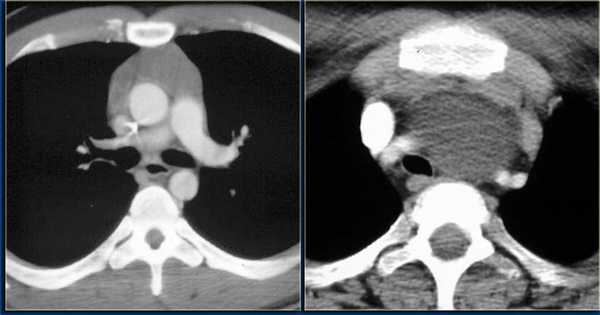

Это более современный вариант рентгенографии, сохранивший ее ключевые особенности: в основе получения изображения лежит рентгеновское излучение, которое, проходя через ткани пациента, по-разному (исходя из их плотности) поглощается и ослабляется ими. Однако важное отличие заключается в том, что компьютерная томография — это совокупность послойных рентгеновских снимков определенной толщины среза, из которых выстраивается объемная проекция, а не плоскость, как на рентгене. В этом (а также в высоком качестве изображения) заключается одно из основных преимуществ компьютерной томографии перед традиционным рентгеновским методом исследования.

Несмотря на более безопасную и эффективную работу современных аппаратов, часто проходить компьютерную томографию все же не рекомендуется из-за возможного воздействия на организм рентгеновского излучения. Тем не менее, компьютерная томография является ведущим методом диагностики заболеваний органов грудной клетки и легких, надпочечников и костно-суставной системы.

Каждый метод дает разную информацию об исследуемых органах. Если говорить в целом, то КТ идеально «видит» легкие, и превосходит все другие методы в выявлении патологии дыхательной системы: и МРТ и рентген и флюорографию.